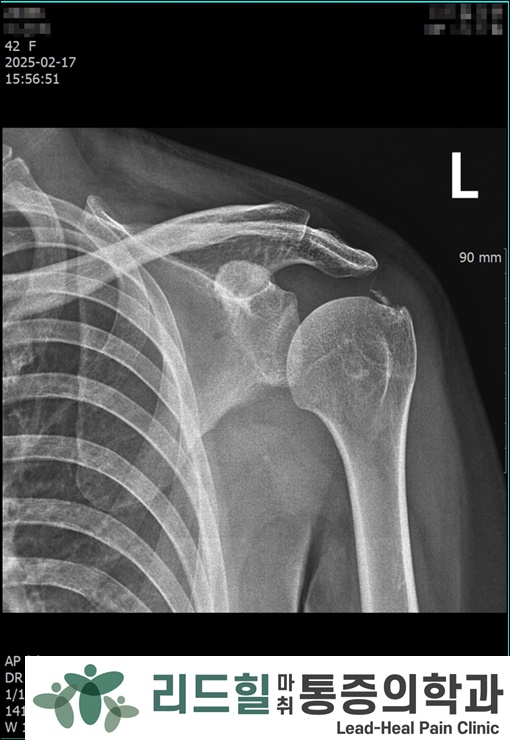

📸 첫 내원 X-ray

좌측어깨 (두번째사진) : 작은 석회 여러 개

좌측어깨처럼 여러 덩어리가 있으면 시술이 조금 더 까다롭습니다.

리드힐에서는 1주 간격으로 3회 석회제거 시술을 진행했습니다.